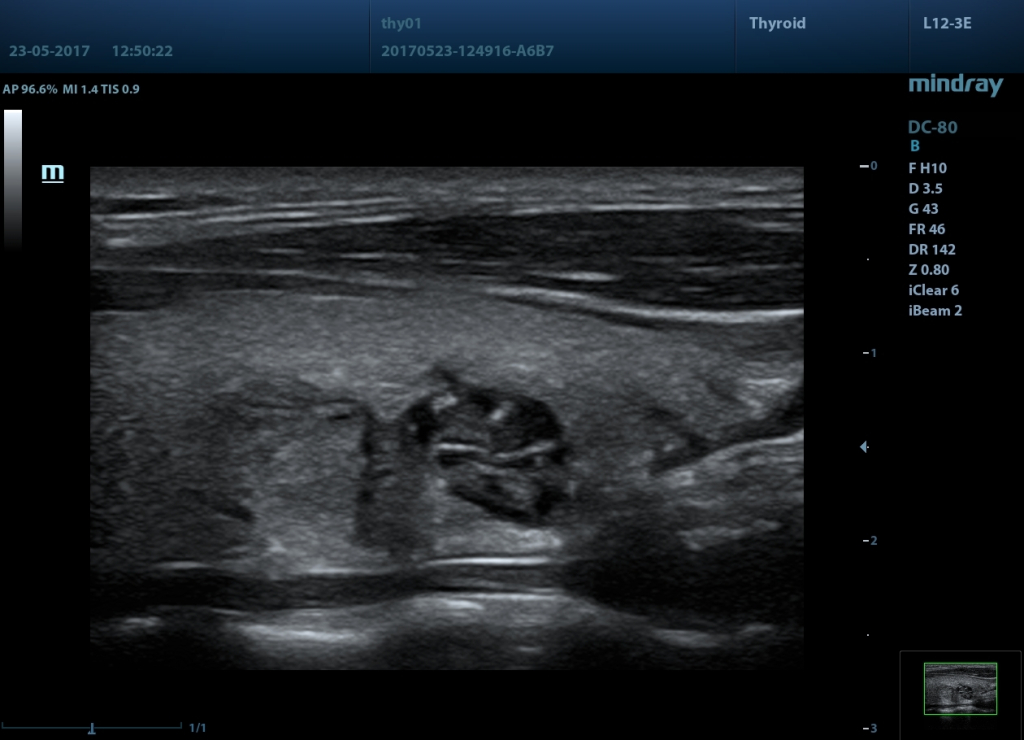

Галерея изображений:

1 - Опухоль щитовидной железы, датчик L12-3E